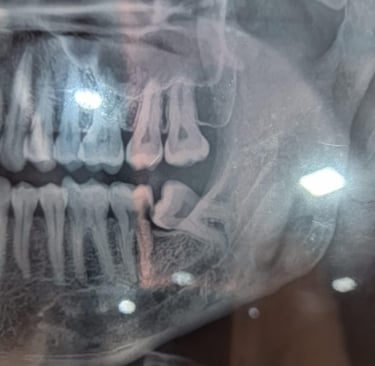

Impacted Tooth Surgery

Impacted teeth may be monitored if symptom-free. Surgery is common for wisdom teeth, while orthodontic aids can help guide tooth eruption.